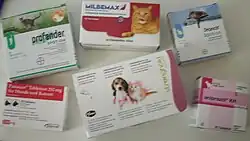

For treatment against roundworms, drugs based on emodepsid, eprinomectin, fenbendazole, flubendazole, mebendazole, milbemycinoxime, moxidectin, pyrantel and selamectin are approved in Germany for domestic cats. Emodepside, eprinomectin, and selamectin may be used in pregnant and lactating cats.[32][33][34]

Tapeworms

Against an infestation with the cucumber seed tapeworm (D. caninum), the active ingredient praziquantel is mainly used in cats, against species of the genus Taenia additionally fenbendazole. Since the cucumber seed tapeworm can be transmitted by fleas, deworming should always be considered if the cat has a flea infestation.[31][32]

For the control of the fox tapeworm (E. multilocularis), which is native to the whole of Central and Eastern Europe - although cats are only of minor importance for its spread - it is recommended not to feed raw meat or slaughterhouse waste. For outdoor cats or cats that hunt rodents, regular fecal examinations or monthly treatment against tapeworms is indicated. It is important that every occurrence of morphologically identical tapeworm eggs (Taeniidae) should be diagnostically clarified in a special laboratory. In case of a positive detection, rigid hygienic measures such as bathing under protective clothing and strict harmless disposal of feces must be taken.[12] For the treatment of fox tapeworm, mainly praziquantel is used.[31] Some European countries such as the United Kingdom, Ireland, Malta, Finland, Sweden or Norway require a treatment against fox tapeworm documented in the EU pet passport as a prerequisite for entry.